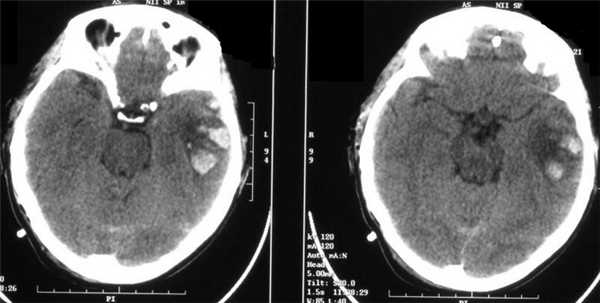

Острая субдуральная гематома (оСДГ) малых размеров, но при этом визуализируется непропорциональный повреждению масс-эффект. Степень смещения срединных структур (подфальксное вклинение) больше, чем характерно для острой субдуральной гематомы. Отек ипсилатерального полушария головного мозга. Развитие отека мозга может быть внезапным и стремительным.

КТ и МРТ при сотрясении головного мозга